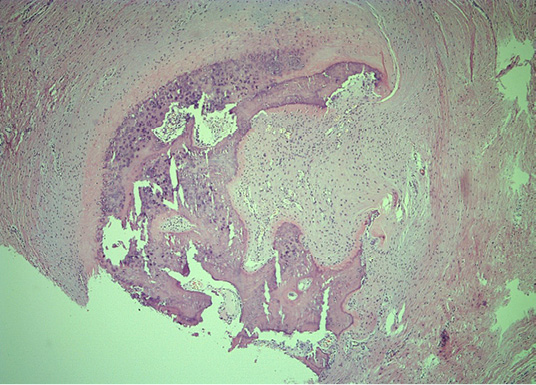

Microscopically, mature cortical and trabecular bone can be seen on the samples taken. The bone trabeculae are thin and widely separated, and between them is bone marrow, built of mature adipose tissue with multifocal hematopoietic activity. Peripherally, the cortical bone is adjoined by collagenous connective tissue and mature adipose tissue, with and easily expressed lymphocytic inflammatory infiltrate with perivascular distribution. In one part of the surrounding connective tissue, the process of forming new bone tissue, represented by primary bone tissue, can be seen (Figures 4–7).

Figure 5. Histopathology revealed mature bone tissue with bone marrow and peripheral fibrous tissue, with no evidence of atypia or malignancy (He&Eo staining. Magnification ×40)

Figure 6. Histologic section of the HO showing mature bone tissue and bone marrow with fat cells and haematopoiesis (He&Eo staining. Magnification ×40)

Figure 7. Representative peripheral area, demonstrating woven bone and compressed fibrous pseudocapsule on the lesions’ exterior (He&Eo staining. Magnification ×40)